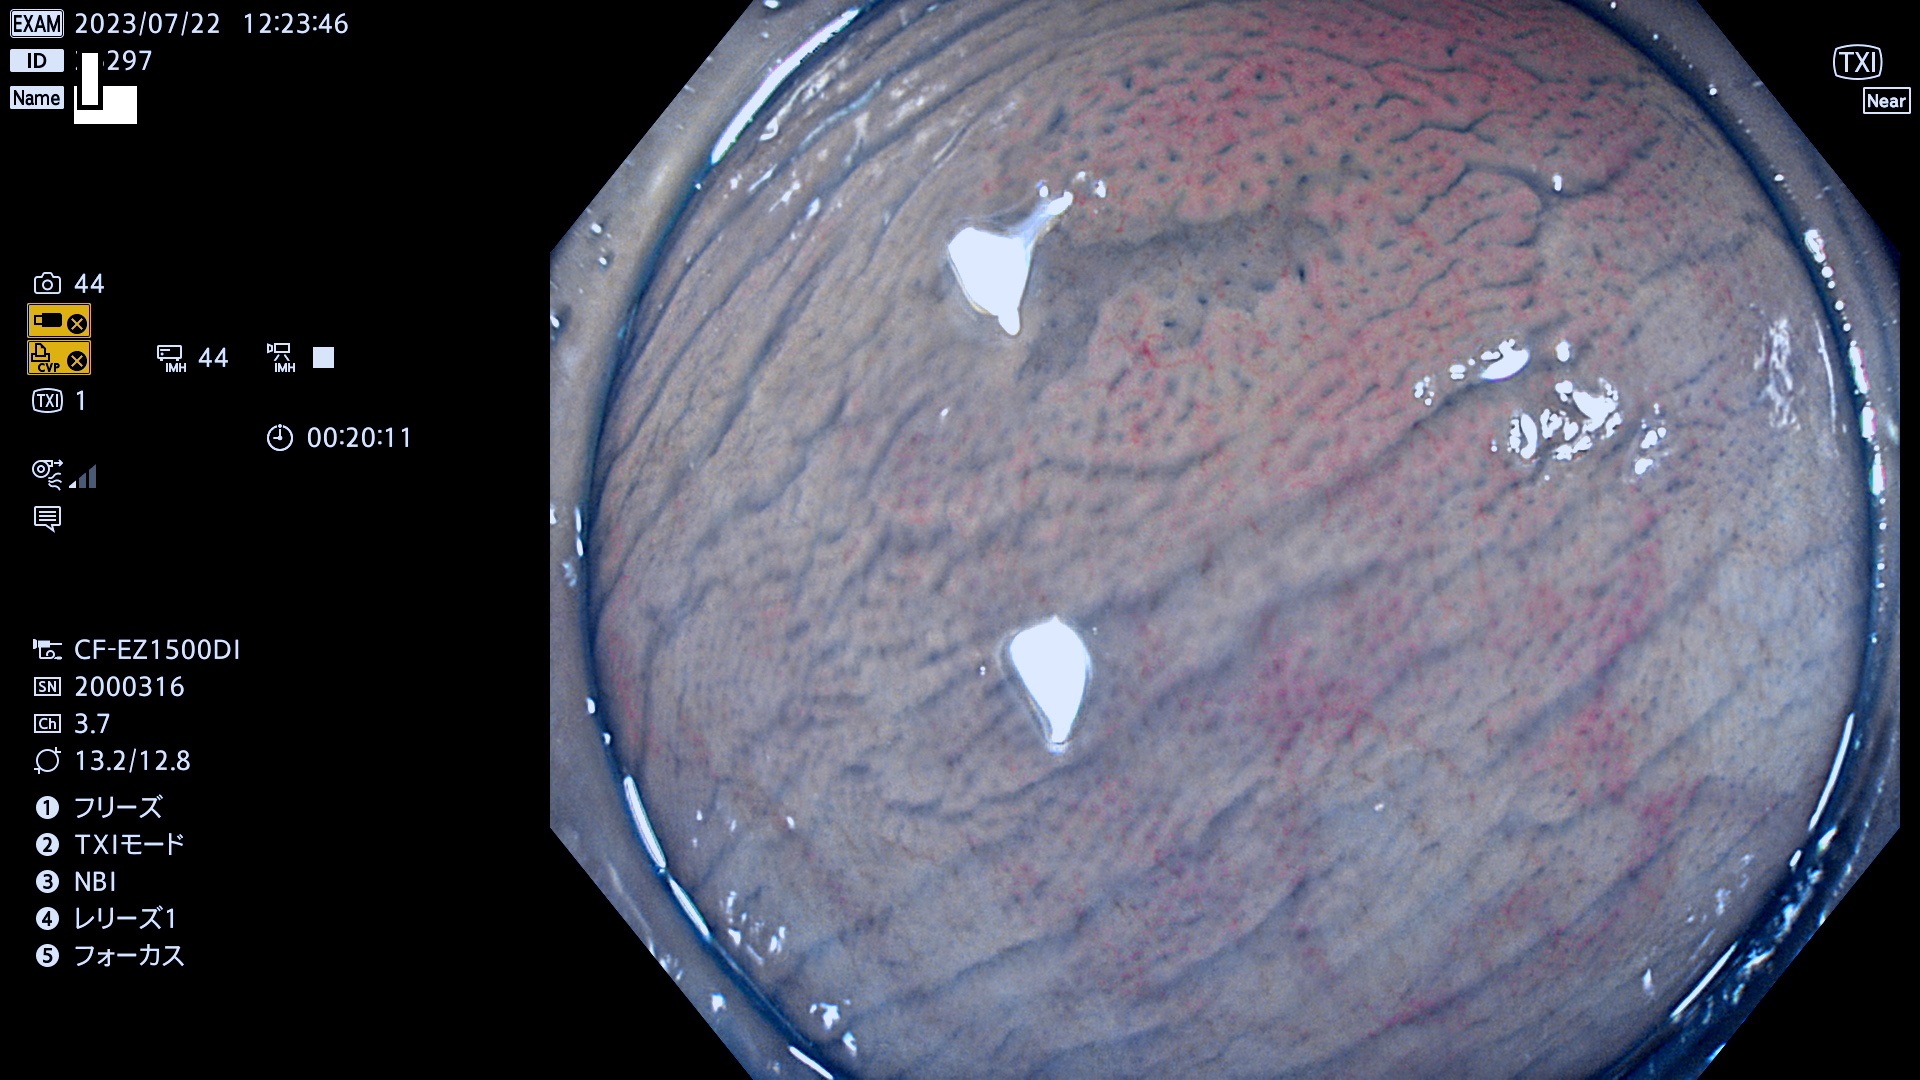

「表面型腺腫(Flat Adenoma)の中で、完全に平坦な物をUb、陥凹している物をUcと呼びます。平坦隆起型(Ua)よりも、発見が難しく危険な病変です。このタイプは「内視鏡後・大腸癌の重要犯人」であり、この発見率は「腺腫発見率」よりも、重要な意味があります。

毎週の検査(木・金・土・日)に発見されたUb、Uc型・腺腫を、その週の日曜の夜にUPし1週間、提示します。

抽出の対象期間 2023年7月20日(木)〜7月23(日)の4日間(48件の検査)12件